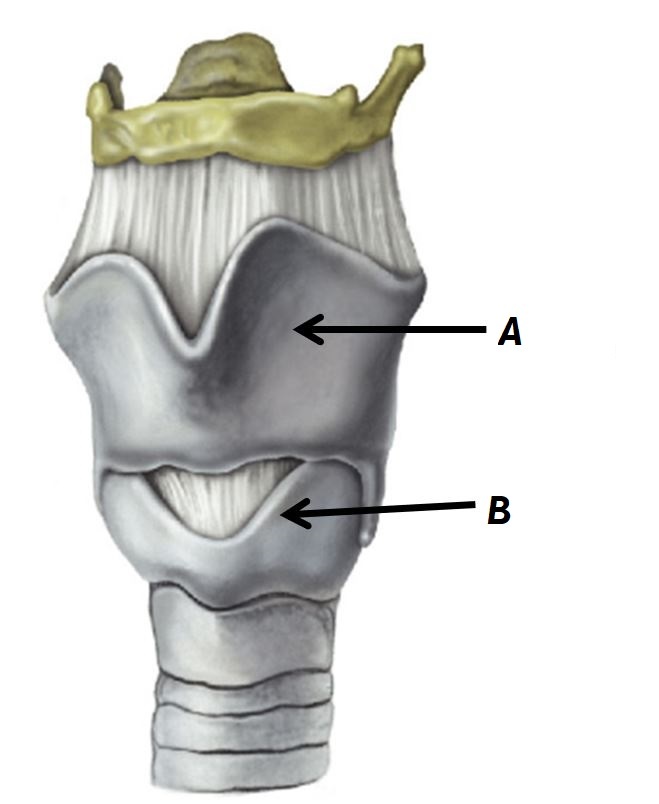

Name structures A and B

A - Thyroid cartilage

B - Cricoid cartilage

Name structures A and B

A - Thyroid cartilage

B - Cricoid cartilage